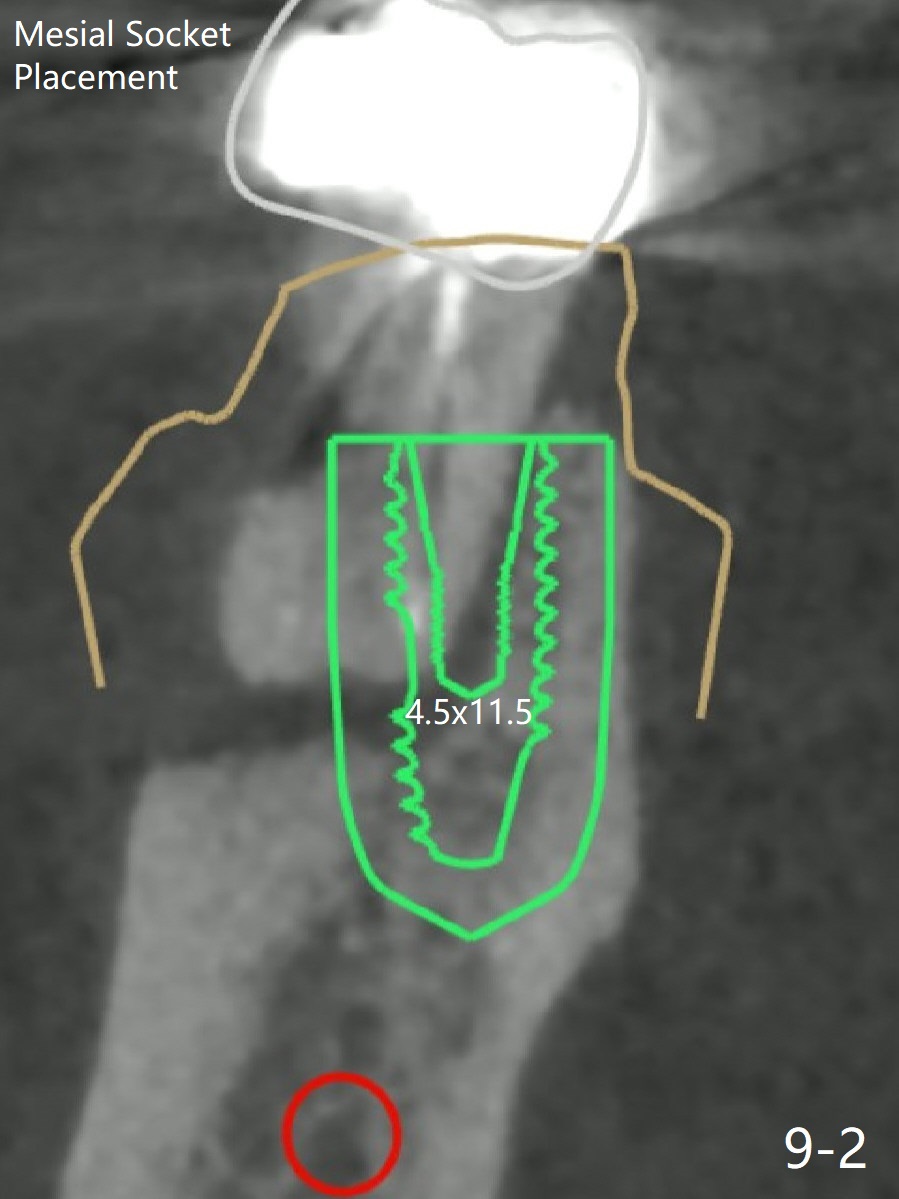

When the tooth #30 is extracted, the gingiva buccal to the septum (S in Fig.1,2 (P: papilla between the mesial and distal roots)) collapses. The latter is fixed with placement of a 4.5x11.5 mm implant (with guide), a 5.2x4(5) mm cemented abutment (Fig.3) and mixture of cortical bone (125μm – 850μm) and cortical/cancellous bone (.5-1 mm) with PRF (sticky bone, B in Fig.4-6). After placement of 2 pieces of PRF membrane over the bone graft, a temporary crown is fabricated to cover the buccal defect (Fig.7 T). Approximately 7.5 mm of the buccal threads are covered by the thick layer of bone graft (Fig.8 B). It is amazing to expect that the bone graft will turn into the buccal plate. It would be better if a narrower implant (4 instead of 4.5 mm) were placed more lingually or there were < 4 mm implant thread exposure (Fig.9). The gingiva reacts to the provisional nicely 7 days postop (Fig.10). The provisional will be removed for modification in 1 month. The patient complains of bad smell from the provisional 2 weeks postop. The provisional is removed. The distal socket (Fig.11 D) is healing, whereas the buccal bone graft (Fig.12 B) seems not have been vascularized. Pedicled flaps (I) should be transferred to cover the buccal bone graft. The margin of the provisional is polished, becomes short, and covered by periodontal dressing, which dislodges 2 days later. One week later, granulation tissue is forming apically with use of oral antibiotic and water jet (Fig.13 *). The bad smell reduces. The superficial loose bone graft changes colar and becomes detached 1 month 10 days postop. The temporary crown with the shortened buccal shelf is reseated for self cleansing or reapplication of PRF if needed (Fig.14).